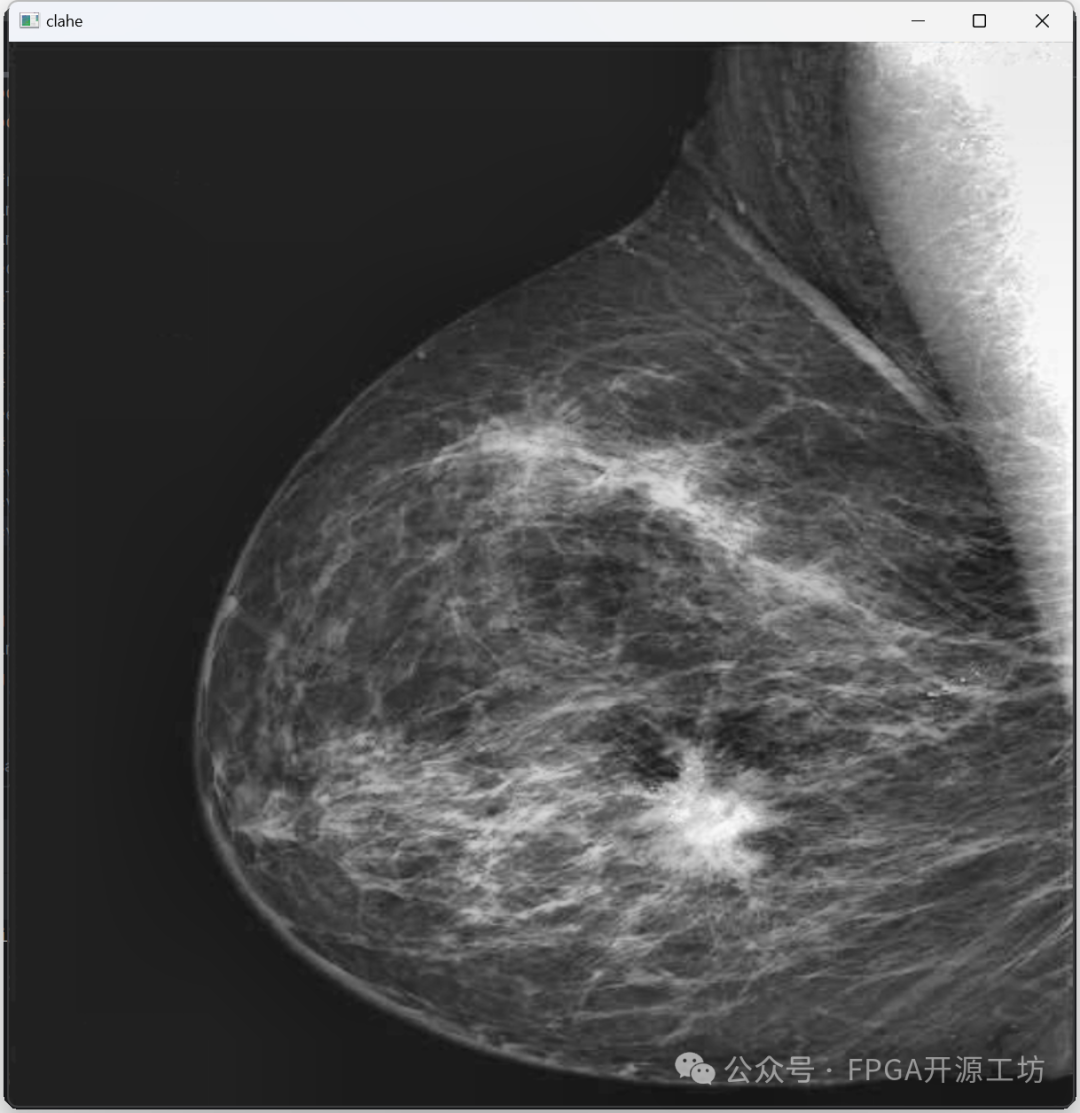

来看一下最后结果,没有一块一块的斑点了。

CLAHE算法就是这些,一共分为下面几步:

对整幅图像进行分块,然后在每一块上面分别进行直方图均衡化操作

在进行直方图均衡化的时候进行CLIP操作

进行线性插值